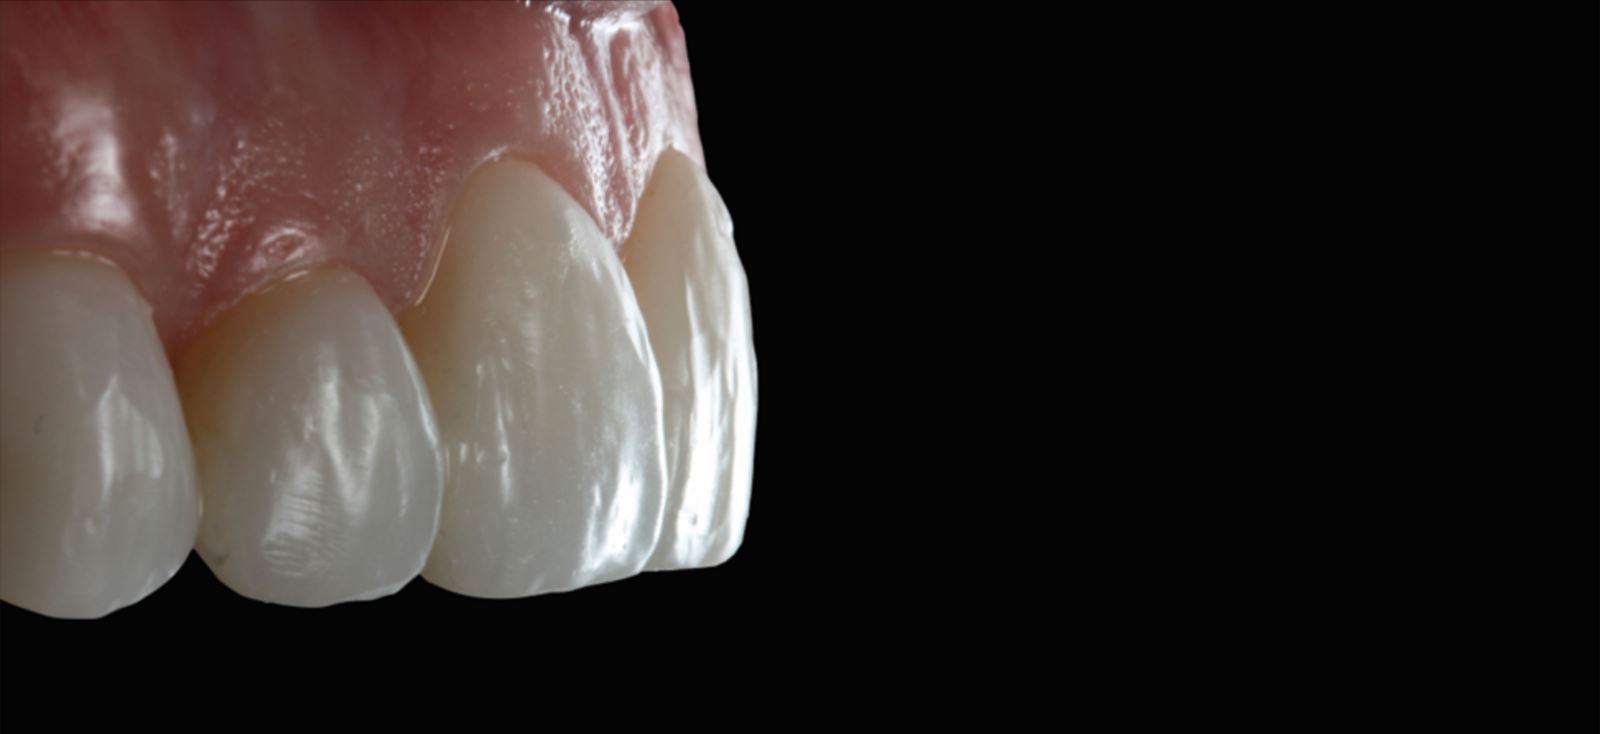

Leštenie a príprava na cementáciu:

Fazety boli kontúrované a vyleštené pomocou leštiacej sady Jiffy™ Natural, čím boli pripravené na cementáciu.

Modelácia anatómie faziet

Na modeláciu anatómie faziet bola použitá diamantová brúska v tvare lopty na rugby a dlhý tenký diamantový brúsok. Na vytvorenie línií Retzia (SR lines) bola použitá lobulárna diamantová brúska (segmentovaný, „laločnatý“ tvar). Počiatočné leštenie prebehlo s Jiffy™ Natural, finálny lesk bol dosiahnutý prípravkom Ultradent Diamond Polish Mint a Jiffy Goat Hair Brush (nie je dostupný v Európe), aby nedošlo k odstráneniu terciárnej anatómie.